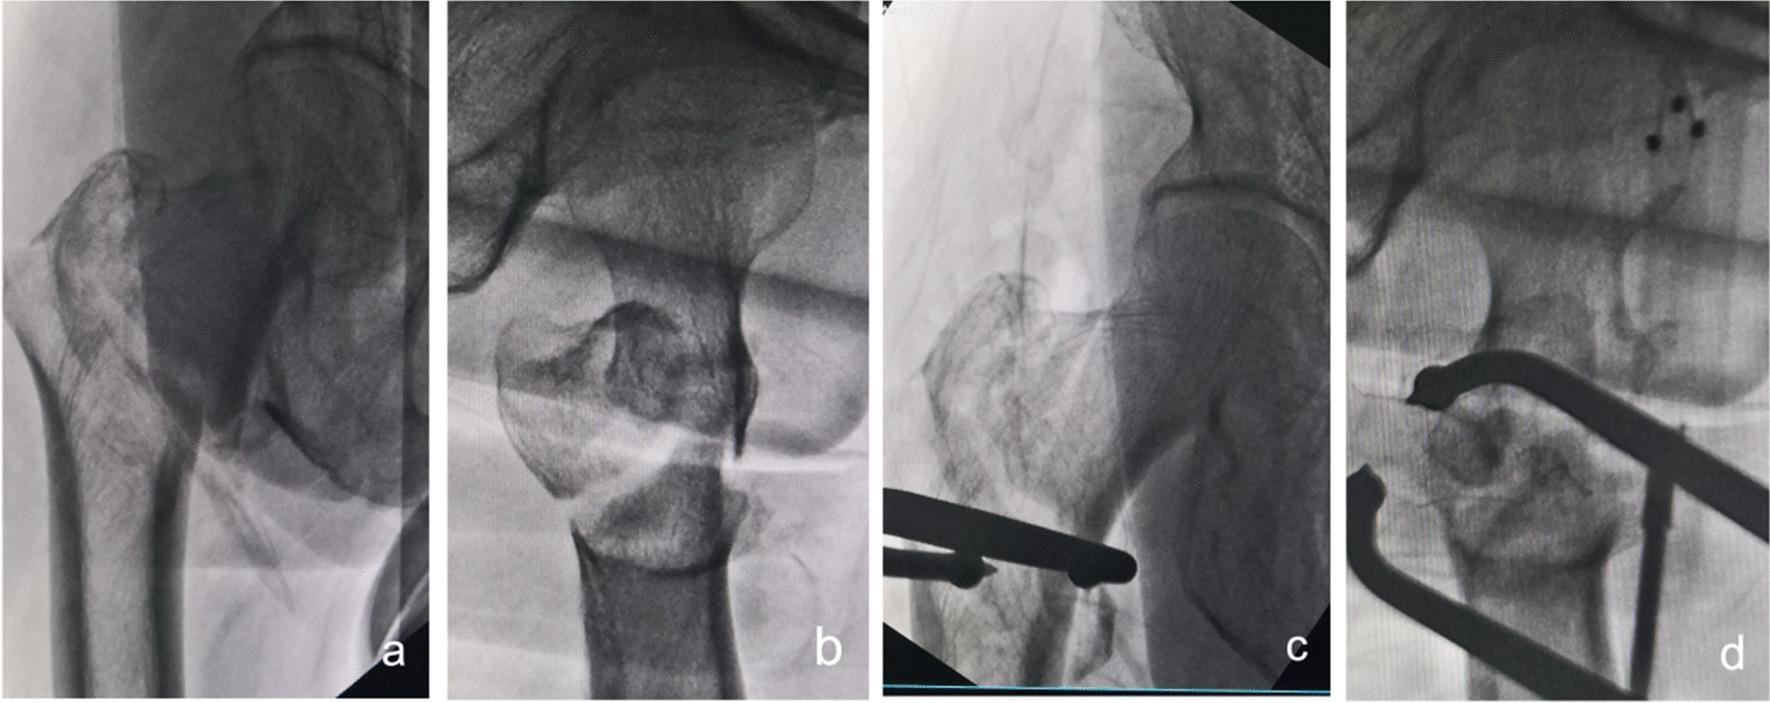

Fig. 10.

Anteroposterior and lateral X-ray films before and after reduction in patients with difficulty in reduction associated with the lateral wall a, b Before reduction; c, d After reduction

Fig. 11.

Anteroposterior and lateral X-ray films before and after reduction in patients with difficulty in reduction associated with proximal femoral fracture displacement a, b Before reduction; c, d After reduction